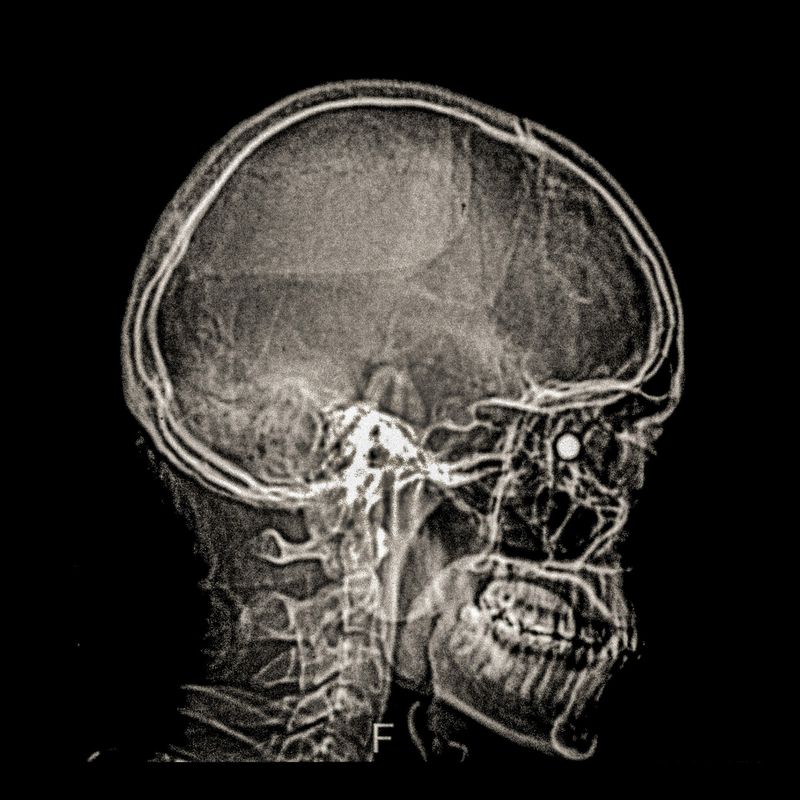

X ray showing the embedded pellet of Camilo Galvez (24) injured by chilean police during Santiago protests.